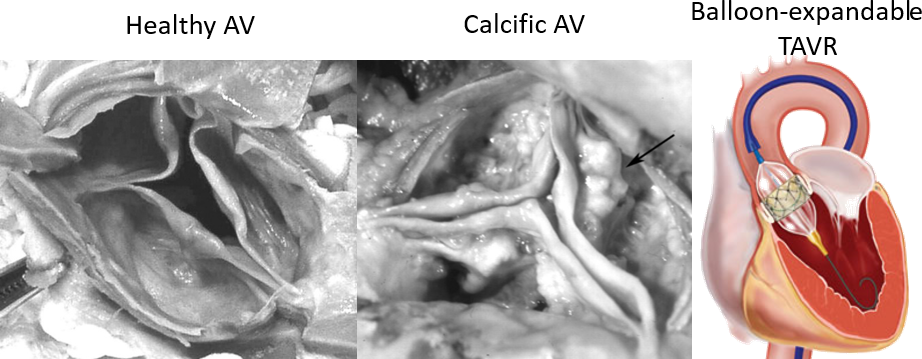

- Calcific aortic valve disease is a cardiovascular condition that causes the progressive narrowing of the aortic valve (AV) opening, due to the growth of bone-like deposits all over the aortic root (AR).

- Transcatheter aortic valve replacement (TAVR) is a minimally invasive procedure that has recently become the only lifesaving solution for patients that cannot tolerate the standard surgical valve replacement.

- This technique comprises of a prosthetic valve mounted on a stent and deployed inside the pathologic native valve.